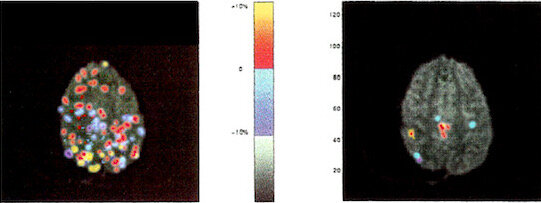

Dr. Walls-Kaufman graduated from Palmer College of chiropractic, the birthplace of chiropractic, in 1980 and was the student newspaper editor. The profession was badly split at the time and the doctor learned the only fair way to control his own political bias as an editor was to always write the strongest possible argument for the political opposition. At Palmer, he learned chiropractic’s brain-first power to cure and heal would cure 80% of all cases, with 10% not improving, and 10% getting worse.

Damned if chiropractic practice wasn’t that breakout exactly. He was stunned that chiropractic’s world-beating ability to cure nearly anything did not grow and conquer hearts and minds as it had from its birth in 1895 until its Golden Age in the 1920s. The reason was that human beings are social animals who will often ignore even miraculous healing when it falls outside the social, political, monetary box – where American Pharma dominates, especially in America. He saw this astonishing unimaginative conservative blindness was at its worst in Washington DC, where $300M in annual Pharma giving ($300M each for Congress and NIH) kept American healthcare toxically captured. The doctor sees the “Big Two” changes needed to transform US and world health are 1) overturning the capture of Pharma and Big Food, and 2) the complete social education and implementation of CBP chiropractic analysis across the world.

Humanity MUST grasp the twin principles of nutrition and the structure of the body being like a musical instrument that relates precisely to brain and nervous system regulation and connection. Otherwise healthcare will never make complete sense and will always crush national budgets whether healthcare is privatized or socialized.